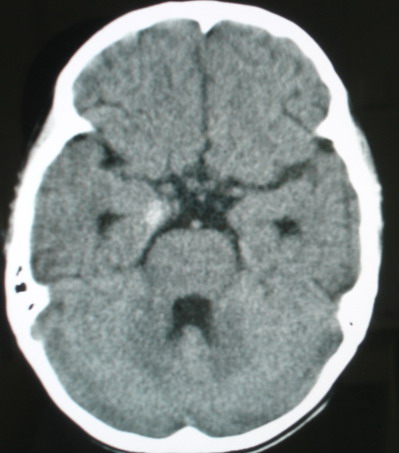

m/8y/,右侧眼睑下垂数日,发育良好,无外伤史,无头痛、恶心、呕吐,学习成绩良好。

ct意见:1、颅内血管畸形。2、右侧海绵窦血管瘤(颈内动脉海绵窦段动脉瘤)。3、脑萎缩。4、建议mr或dsa.

增强片